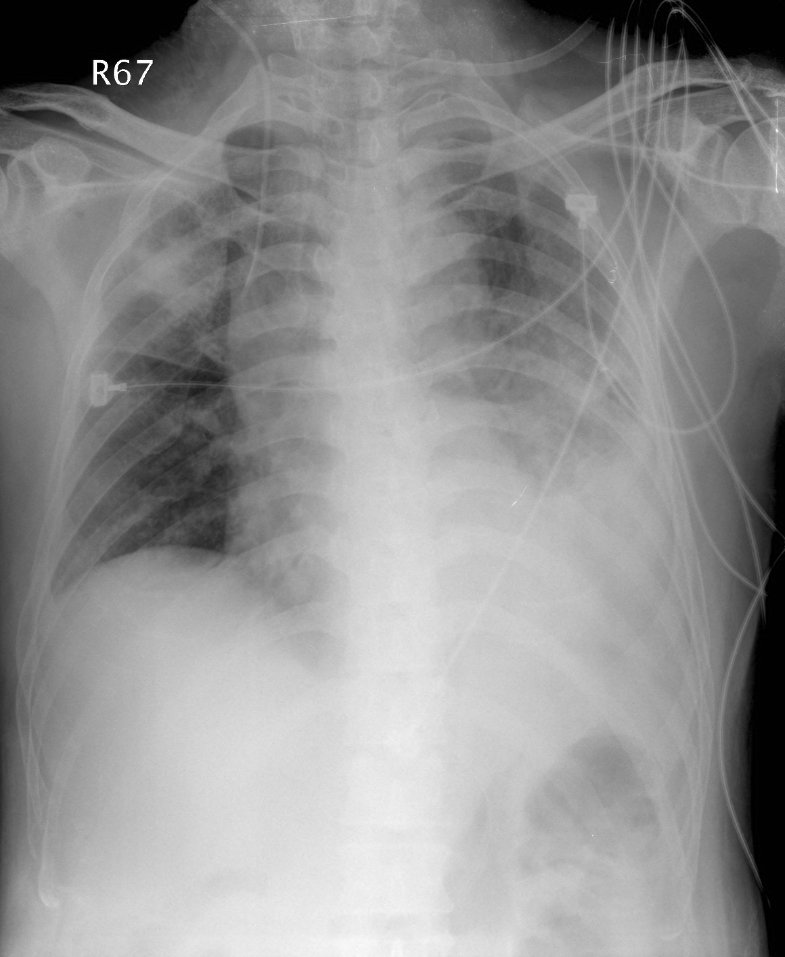

這題的解題核心在於將病患的旅遊史、特殊臨床症狀(如腹瀉、意識不清、低血鈉)以及痰液檢查結果(大量白血球但無革蘭氏染色陽性菌)與胸部X光影像的廣泛性肺炎表現結合起來,指向特定的非典型肺炎病原體。圖片中雙側廣泛的肺部浸潤,特別是左側大片實變,顯示病患有嚴重的肺炎。